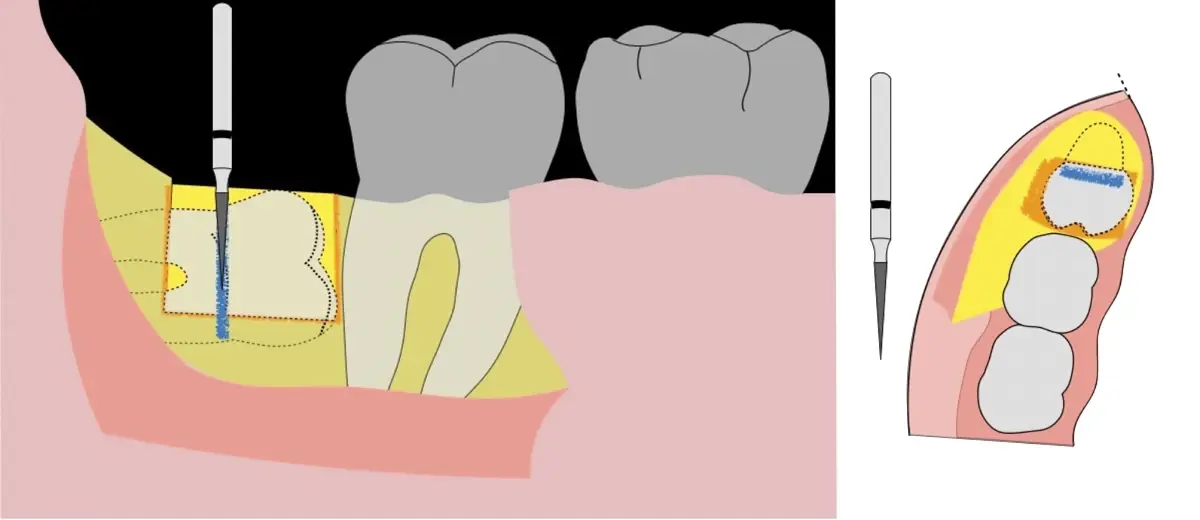

En contraste, el instrumento piezoeléctrico utiliza un corte micrométrico que retira un área de superficie mínima de hueso, y reduce el riesgo de termonecrosis marginal en comparación con las fresas rotatorias convencionales.9 Los micromovimientos mejoran la precisión en el corte y el control táctil, y eliminan las macrovibraciones que se producen con los instrumentos rotatorios.10 Su frecuencia de oscilación es la amplitud de 60-200 μm horizontalmente y de 20-60 μm en sentido vertical, lo que es muy inferior en comparación con las micro sierras oscilantes; por lo tanto, proporciona cortes de osteotomía precisos y seguros. Adicionalmente, posee vibraciones ultrasónicas que descomponen el líquido de irrigación en partículas muy pequeñas (fenómeno de cavitación, que produce un efecto hemostático y así reduce la pérdida de sangre), lo que proporciona una visión clara y sin obstáculos del campo quirúrgico11,12.

El procedimiento se inicia colocando anestesia troncular para bloqueo del nervio dentario inferior y sus ramas. Luego, se establecerá el diseño de acceso según la disposición de la molar a extraer. Para fines didácticos, se explicará cómo se realizaría la extracción de la molar de la Figura 1: se realiza una incisión horizontal a nivel de la zona retromolar hasta llegar a distal de la segunda molar, continuándose con una incisión intrasurcular hasta mesial de la segunda molar, finalizando con una incisión vertical a espesor total hasta llegar a la línea mucogingival (Figura 2).